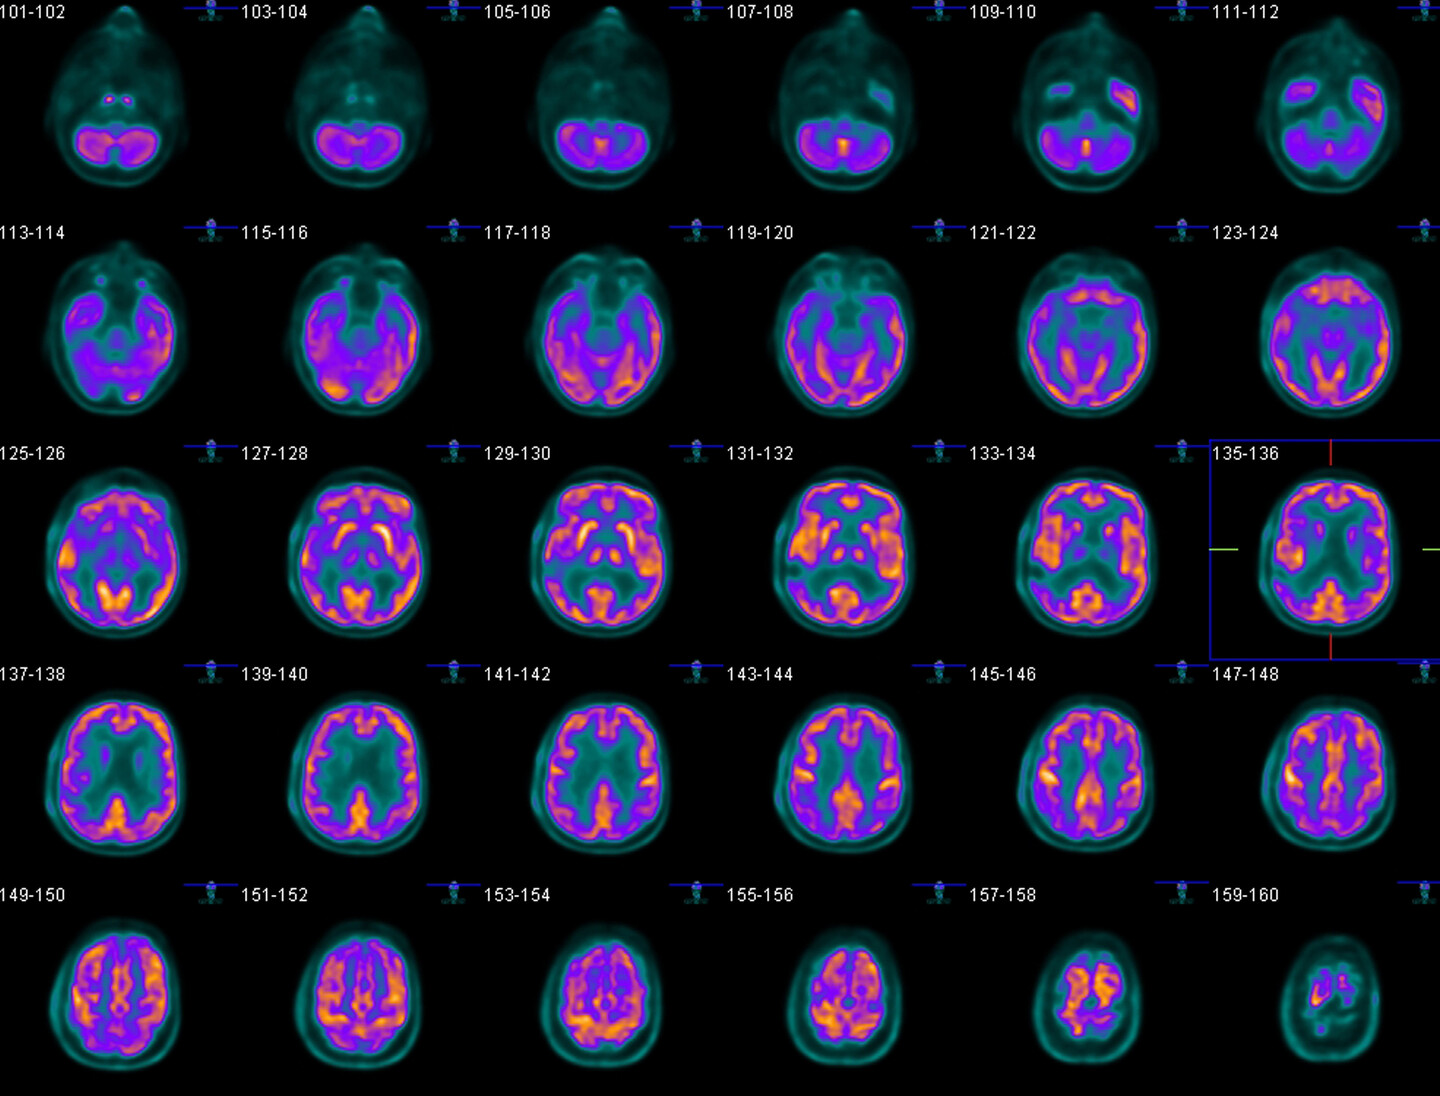

One of the most important biomarkers for Alzheimer’s is a protein called beta-amyloid. This protein makes up amyloid plaques, a brain abnormality that is a hallmark of Alzheimer’s disease. While amyloid plaques are most plentiful in the brains of patients with severe Alzheimer’s dementia, they begin accumulating long before patients notice any memory issues.

The fact that amyloid plaque buildup precedes memory loss has made the protein a prime target for researchers who want to study early-stage Alzheimer’s disease. Scientists believe that if a treatment is developed, it will work best if administered early, before Alzheimer’s has damaged the brain too extensively.

“There’s been a push in research studies to find people who have these biomarkers and are cognitively unimpaired,” Largent says. While having high amyloid levels doesn’t guarantee that a person will develop dementia down the line, it greatly increases the risk level. That makes people with high amyloid levels ideal candidates for clinical trials testing early interventions.